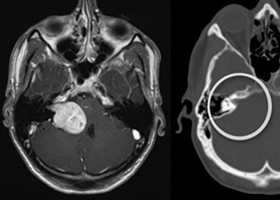

Наиболее информативным методом выявления вестибулярных шванном является МРТ головного мозга с контрастным усилением в режиме Т1 и Т2. Это исследование позволяет определить размеры опухоли, наличие перитуморозного отека, наличие признаков окклюзионной гидроцефалии, которая может быть следствием сдавления опухолью IV желудочка. Кроме этого МРТ позволяет провести дифференциальную диагностику с другими опухолями схожей локализации (чаще с менингиомой задней грани пирамиды височной кости). Еще одним стандартом диагностики является КТ в костном режиме. Независимо от снижения слуха стандартом является проведение аппаратной аудиографии.